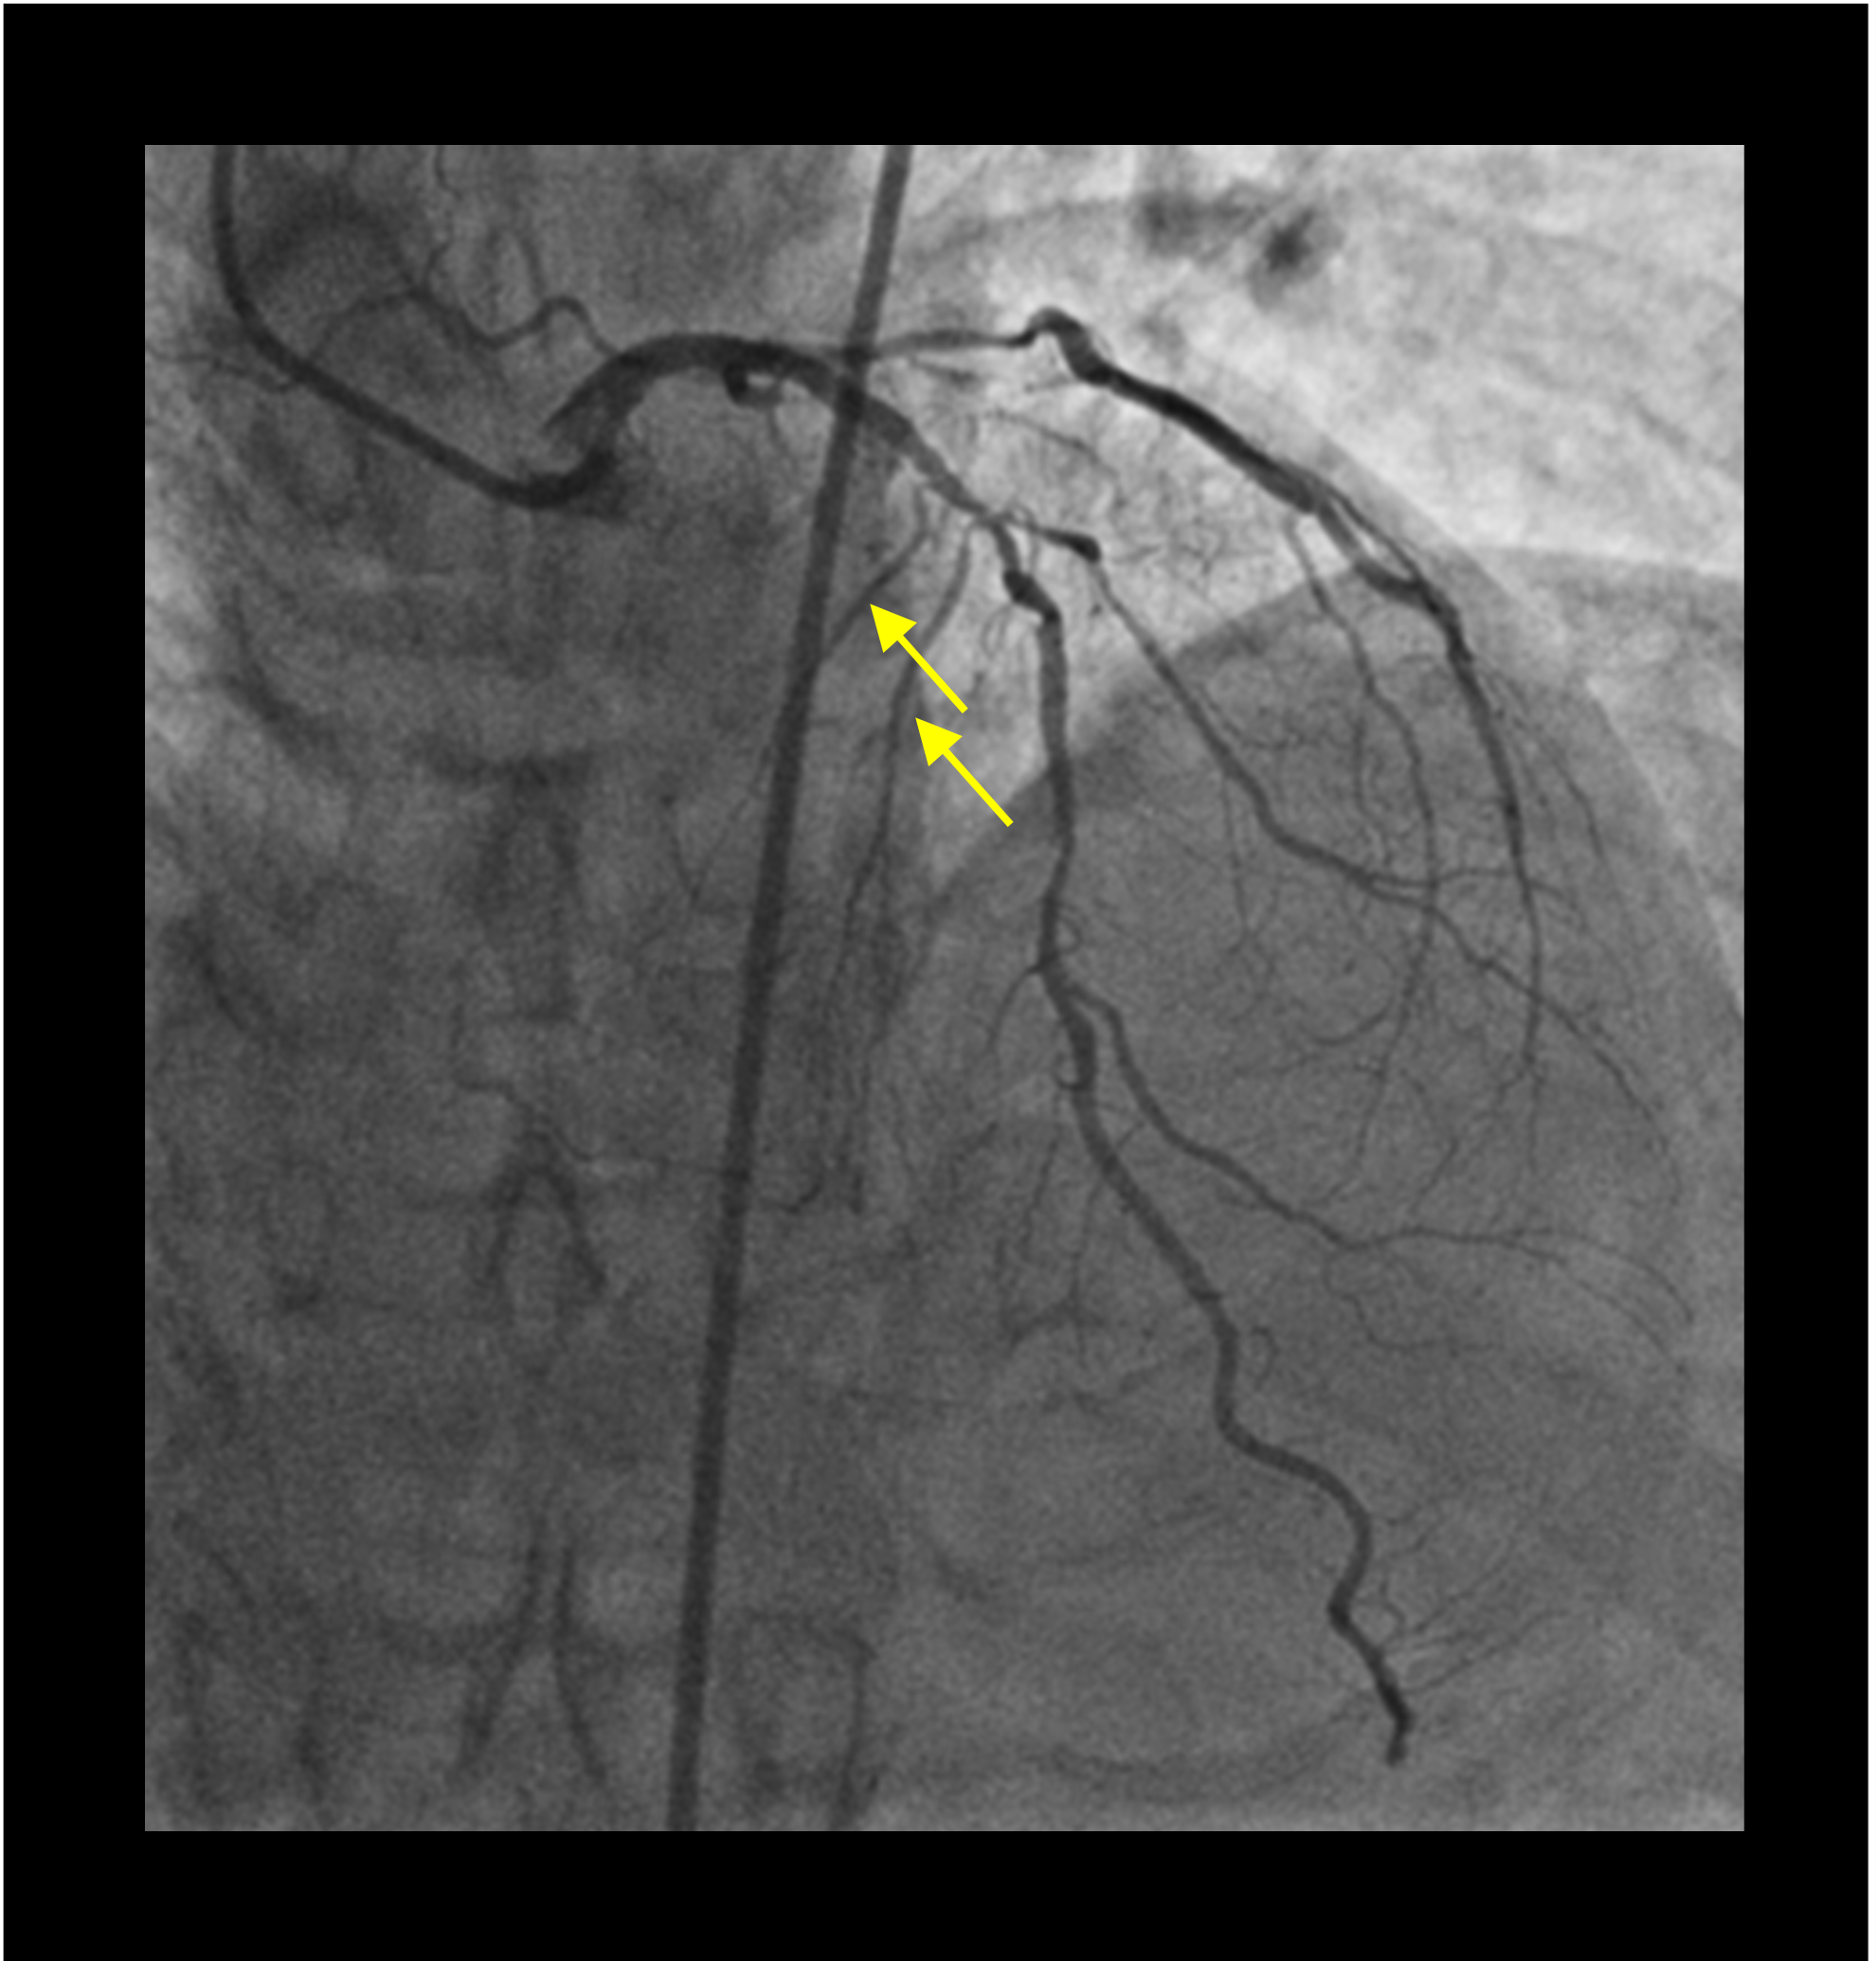

Following a multidisciplinary discussion, it was decided to proceed with multivessel percutaneous coronary intervention. The patient underwent successful intervention of the LAD following calcium modification with rotablation involving the placement of 3 second-generation drug-eluting stents. Routine postprocedural electrocardiography showed a sinus rhythm with evidence of new onset bifascicular block (Figure 2A and B). On postoperative day 2, the patient developed recurrent episodes of syncope at rest; telemetry during these episodes showed complete heart block. Repeat coronary angiography showed patent stents with occlusion of the first and second septal perforators (Figure 3) manifesting as complete heart block by infra-Hisian ischemia. In cases of infra-Hisian ischemia, the major septal perforator courses along the interventricular septum towards its right side and arborizes prior to the moderator band supplying the infra nodal conduction system.1 Occlusion of these septal perforators due to atherosclerosis,2 thrombosis following alcohol septal ablation,3 and injury during aortic valve surgery is associated with development of infra-Hisian conduction blocks.

The patient was monitored for spontaneous resolution with backup temporary transvenous pacing (Figure 2C). Coronary intervention to the occluded septal would have been technically challenging and carried the risk of main vessel stent distortion. We thus proceeded with a dual-chamber permanent pacemaker implantation for persisting complete heart block.